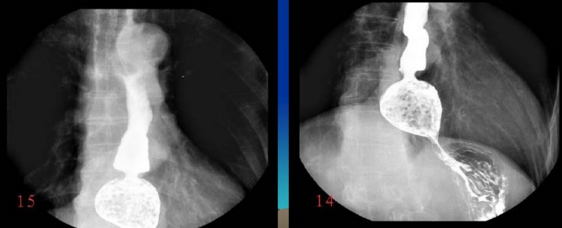

很多人沒有接觸到數字胃腸一體機,可能對它還比較陌生。其實它是一款多功能數字造影胃腸機,功能強大,操作便捷,可以真正實現數字化攝影,以及無膠片化管理,配置先進的工作站,可以保證其圖像畫質。同時它在臨床上的應用也比較的廣泛,能夠檢查多種疾病。下面,由普愛醫療小編詳細列舉一些。

1、食道造影。

2、選擇性小腸造影。

3、氣鋇雙重對比造影。

4、消化道支架置放。

5、食道支架。

除了上述列舉的一下臨床應用之外,還有胃腸道常見疾病,比如:炎癥、潰瘍、腫瘤等疾病,都可以通過利用數字胃腸一體機進行檢查,一般應用數字透視,動態以及多方位觀察器官的變化,提供高清晰的圖像畫質,減低了誤診的幾率,提高了治療的效果,如果想要進一步了解更多關于數字化胃腸機產品的相關信息的話,可咨詢:400-025-6366